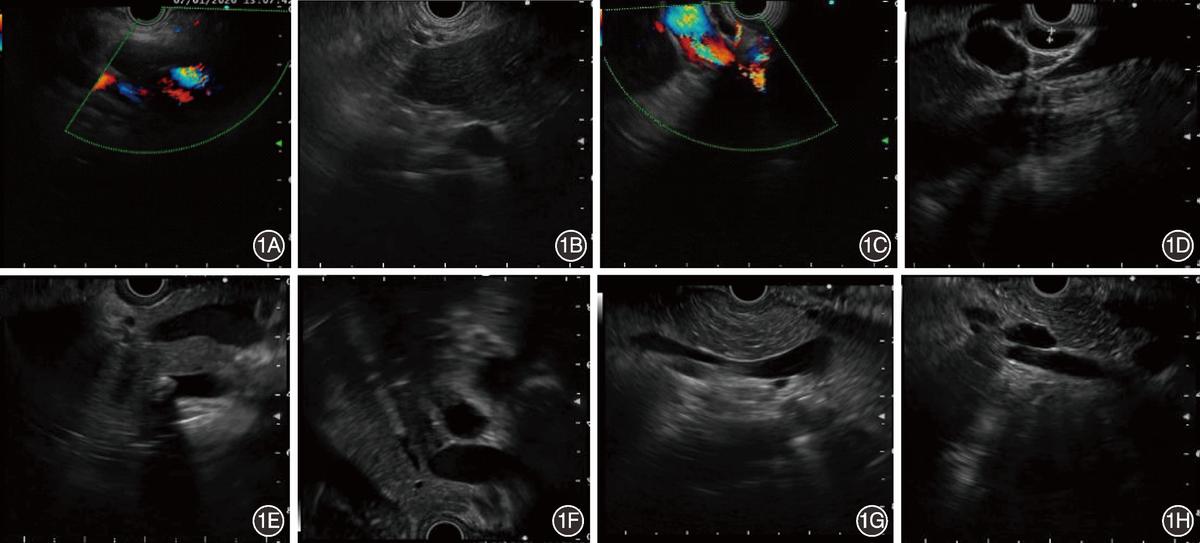

回顾性收集2016年5月—2020年10月武汉大学人民医院消化内镜中心502个病例和武汉协和医院20个病例的EUS视频资料,基于视频截取图像,根据需要将图片分类。标准图像:包含4个站点的标准图像;肝窗标准图像:超声探头位于肝窗站点时的标准扫查图像;胃窗标准图像:胃窗站点的标准扫查图像;球窗标准图像:十二指肠球部站点的标准扫查图像;降窗标准图像:十二指肠降部站点的标准扫查图像;非标准图像:除标准图像外其他EUS扫查过程中的超声成像。EUS胆管扫查标准图像示例见图1。

图1 内镜超声胆管扫查标准图像示例 1A、1B:肝窗标准图像示例图;1C、1D:球窗标准图像示例图;1E、1F:胃窗标准图像示例图;1G、1H:降窗标准图像示例图